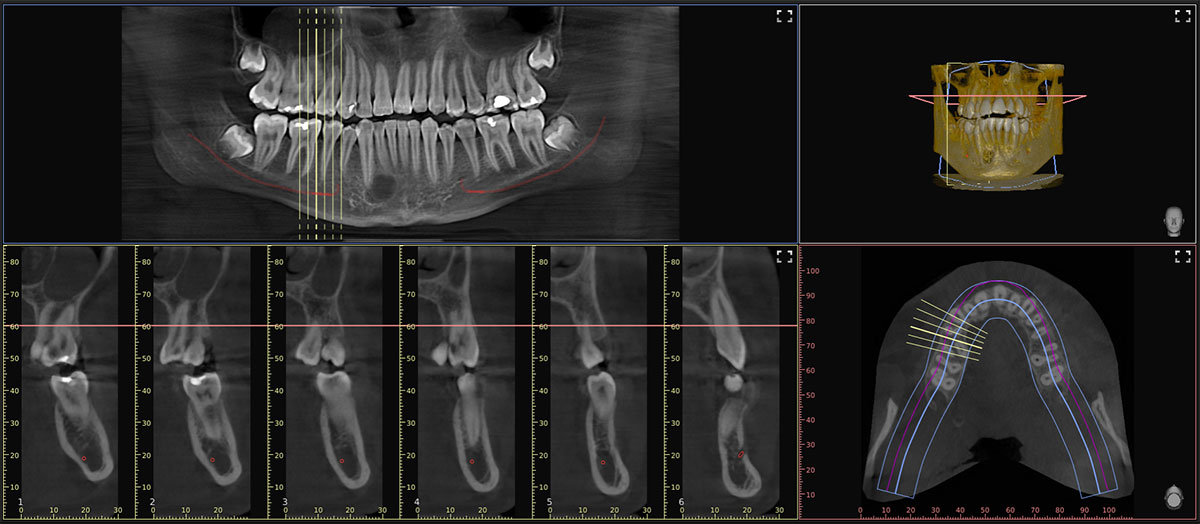

Posizionare il paziente non è mai stato così facile. Basta far mordere il bite e il paziente sarà sempre nella zona a fuoco della macchina: non vi è più la necessità di acquisire immagini di centratura radiologica (Scout View). Appena finito di acquisire l'immagine, l'Intelligenza Artificiale, automaticamente, rimuoverà gli artefatti metallici con il filtro MAR di seconda generazione, leggerà e disegnerà da sola una perfetta Panorex con la porzione ossea e gli elementi dentali perfettamente a fuoco e traccerà il decorso dei nervi alveolari inferiori.

Al professionista non resterà che scorrere i tagli radiologici e dedicare il suo tempo alla risoluzione del quesito diagnostico, eseguendo misurazioni, posizionando template implantari e creando i propri piani di lavoro.